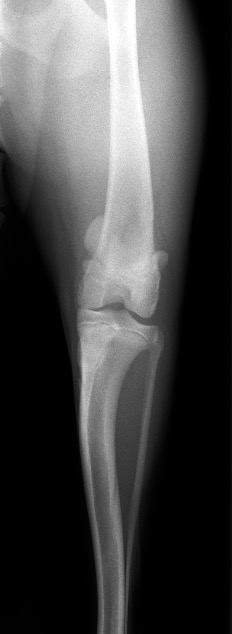

次の2枚の写真はパテラアルタのある今回の子と正常の子の膝関節と膝蓋骨の位置を示したものです。

脱臼時の膝関節

パテラアルタの膝関節

正常膝関節